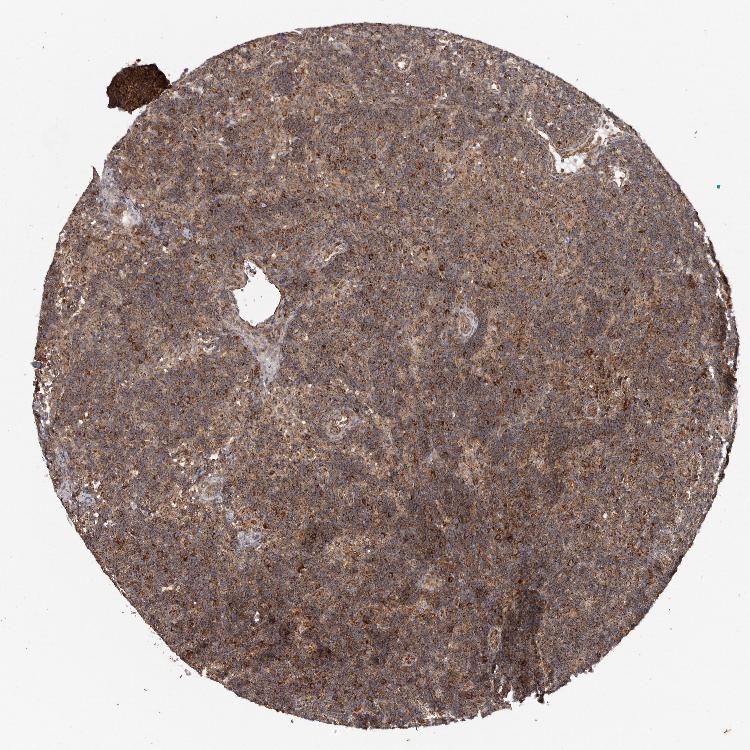

TISSUE PRIMARY DATA LYMPH NODE Show tissue menu

Lymph node

LYMPH NODE - Antibody stainingi

Antibody staining in the annotated cell types in the current human tissue is reported as not detected, low, medium, or high, based on conventional immunohistochemistry profiling in selected tissues. This score is based on the combination of the staining intensity and fraction of stained cells.

Each image is clickable and will lead to virtual microscopy that enables deeper exploration of all samples and also displays staining intensity scores, fraction scores and subcellular localization as well as patient and tissue information for each sample.

Antibody HPA029133Antibody HPA029134

Germinal center cells Not detectedHigh

Non-germinal center cells LowHigh